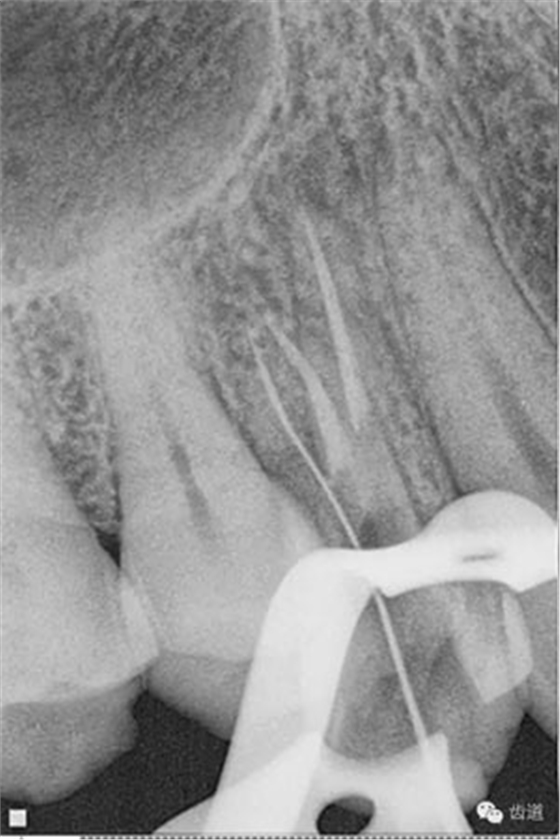

處理:去除暫封物,超聲根管蕩洗,清除氫氧化鈣糊劑,干燥根管,拍片顯示2506牙膠尖適合,根管內(nèi)放置AHplus,熱牙膠連續(xù)波根管充填。

數(shù)碼x攝影顯示:近中頰根及腭根根管充填恰填,遠(yuǎn)中根管有遺漏。

顯微鏡下反復(fù)探查根管,未探及遺漏根管口,放置棉球,zoe暫封。轉(zhuǎn)診上級(jí)醫(yī)生處理。